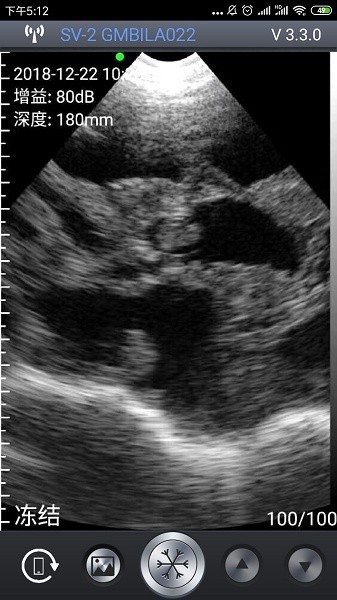

2、实时图像显示:即时呈现超声扫描画面,便于快速查看与初步判断检测结果。

4、智能妊娠识别:基于深度学习算法自动判断母猪妊娠状态,提高诊断准确率。